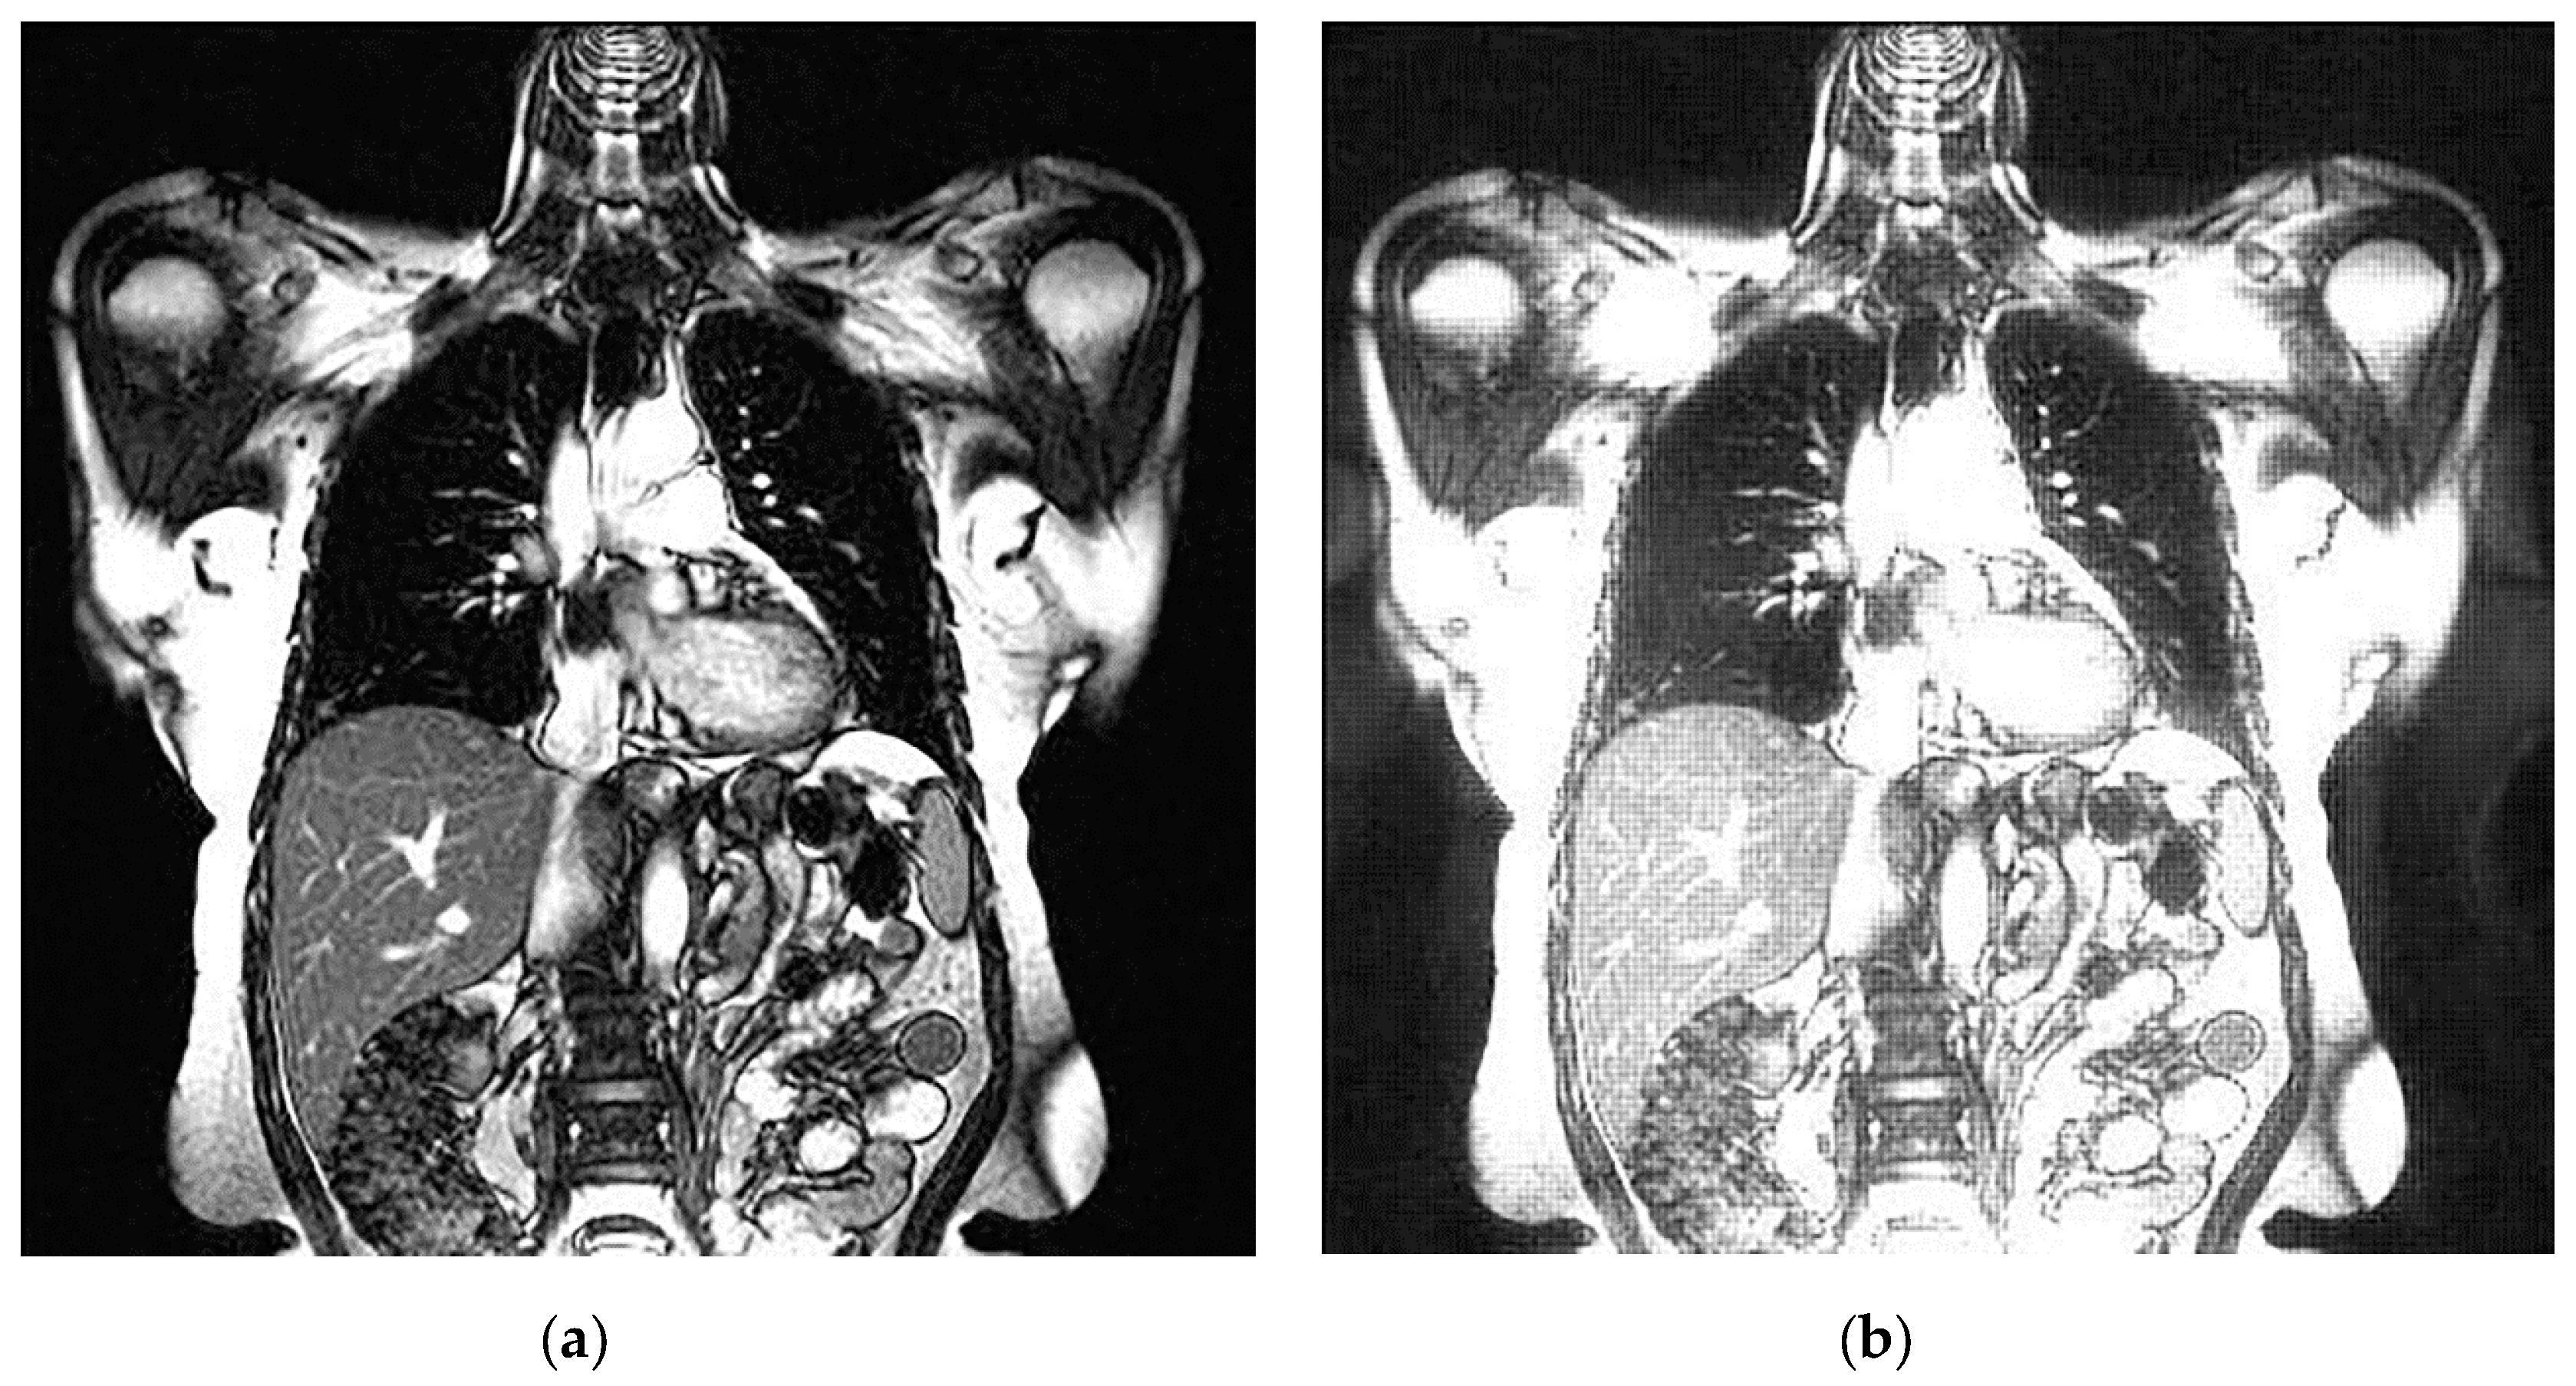

An example of 3D tomographic images “wmri”, “Trufi_COR” and “Body_1.0” DWT with wavelet is shown in Figure 5, Figure 6 and Figure 7 respectively. Frames in Figure 6 and Figure 7 are selected to illustrate the error effect on the image processing result. Figures show a gradual improvement in the quality of processing with an increase the bit-width : in Figure 5b, Figure 6b and Figure 7b visible distortion (Figure 5b is darkened in places, and Figure 6b and Figure 7b are lighted); in Figure 5c, Figure 6c and Figure 7c processed images are indistinguishable by eye from the original images; in Figure 5d, Figure 6d and Figure 7d processed images are identical to the corresponding originals. Experimental results are of higher quality compared with the calculation results. The values dB and at and respectively (Figure 5) obtained after 8-bit image “wmri” DWT with wavelet exceed the corresponding calculated values dB and at and respectively (Table 1). The values dB and at and respectively (Figure 6) obtained after 12-bit image “Trufi_COR” DWT with wavelet exceed the corresponding calculated values dB, dB at and respectively (Table 2). Similarly, for “Body_1.0”.

Figure 6.

Example of 3D tomographic 12-bit image “Trufi_COR” (15-th frame) DWT by wavelet: (a) original image; processed image: (b) , dB; (c) , dB and (d) , .